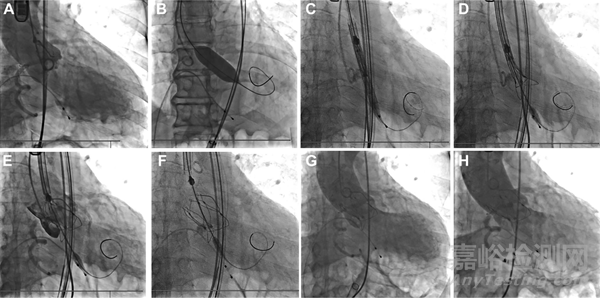

(A)活體透視顯示主動(dòng)脈根部。(B)鈣化主動(dòng)脈瓣處球囊膨脹。(C)傳遞系統(tǒng)。(D)將參考點(diǎn)與正位環(huán)空對(duì)齊后,逐漸展開瓣膜。(E)確認(rèn)瓣膜位置和冠狀動(dòng)脈血流量。(F)完成閥門部署。(G)即刻血管造影顯示中度瓣膜周圍滲漏。(H) 15分鐘后瓣周滲漏減少至輕度。